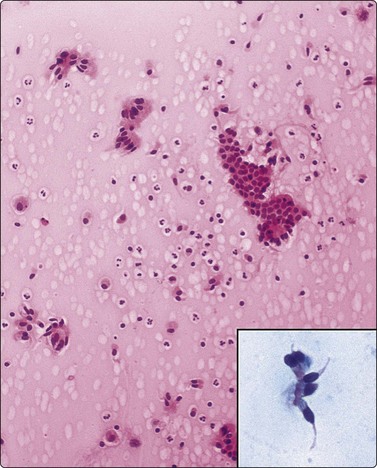

image image

Fig. 8.7 Mycobacterial infection

(A) Negative images of bacilli in a background of granular necrotic debris (MGG, HP); (B) Numerous acid-fast bacilli, including clumps of beaded forms (Ziehl-Neelsen, HP; Inset HP oil).

One can make a confident diagnosis of a ‘granulomatous process’ on aspirated material; however, a more important aspect of the aspiration is to obtain an adequate sample for staining and culture, particularly to distinguish between ‘typical’ and ‘atypical’ mycobacteria101 and for typing fungal organisms. It is best to have a large sample for this purpose and we have not found much value in washings of the needle after a cytology smear has been made. Instead, we advocate sending the whole aspirate for culture. Culture for tuberculosis is more successful in cases with necrotic and inflammatory debris.99,102 PCR can provide a rapid diagnosis, aids in subtyping and can identify drug resistant strains.170,171

Epithelioid histiocytes are fairly cohesive and form granulomas which are often aspirated intact (Fig. 8.5). Epithelioid cells have an elongated or bean-shaped nucleus and abundant cytoplasm which is rather pale and indistinct both in Pap- and H & E-stained specimens (Fig. 8.5). The cytoplasmic density is higher in MGG-stained material. Multinucleated histiocytes can be seen but are usually sparse. They are mainly free of intracytoplasmic pigment or birefringent material, unlike the multinucleated histiocytes seen in non-specific reactions in pulmonary tissue. Caseous necrosis has a variable appearance. There may be an amorphous to granular background with little cell outline visible, but sometimes outlines of necrotic cells may be prominent (Fig. 8.6) and often the appearances are merely of nondescript debris, histiocytes and neutrophils. Dahlgren cites granular calcific material as a common accompaniment.98 Lymphocytes may be plentiful in granulomatous inflammation.

Bailey et al.99 diagnosed 28 of 34 cases of TB by either auramine rhodamine fluorescence or positive culture; acid-fast bacilli (AFB) were seen in only 38% of cases. In Rajwanshi’s102 and Das’s103 series AFB were identified in approximately half of the cases. Gong et al. found PCR to be about 80% sensitive compared to 40% for ZN staining in FNB material.171

Acid-fast bacilli are more often seen in cytological material characterized by a mixture of neutrophils, histiocytes, mucoid or necrotic material than in those lesions with a prominent epithelioid cell component,99,102 though culture is positive in a similar percentage of cases with and without epithelioid cells.103 Whenever necrotic debris is seen, we restain smears with ZN stains. Maygarden described mycobacteria as negative images in a stained background in MGG material (Fig. 8.7).182 Silverman reported negative images in both Diff-Quik and Papanicolaou-stained material in a BAL sample from a patient receiving clofazimine treatment for an atypical mycobacterial infection. The reddish, refractile and polarizable drug-derived crystals can impart a pseudo-Gaucher-like appearance to the cells, simulating the negative images of an atypical mycobacterial infection.183